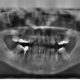

Odbudowa zęba na włóknie szklanym – zalety i przeciwwskazania

Odbudowa zęba na włóknie szklanym to popularny sposób zakończenia leczenia endodontycznego (kanałowego). Zabieg…